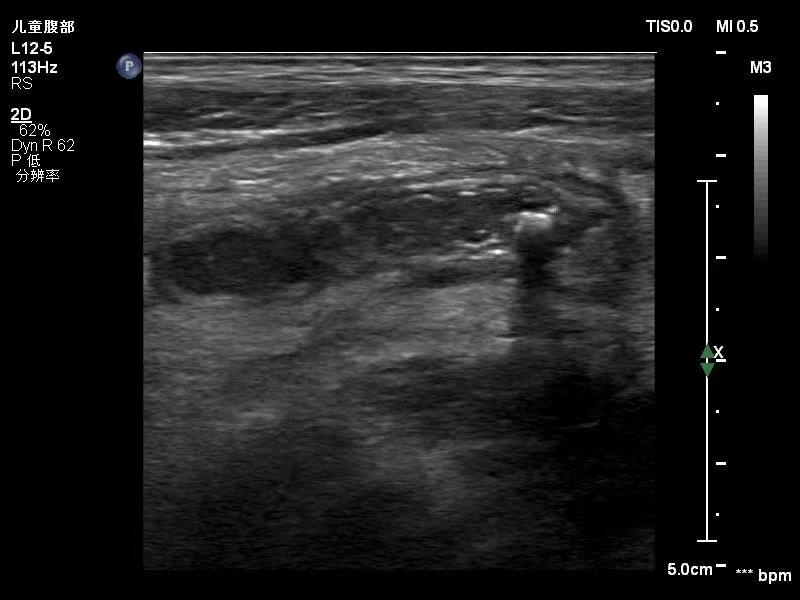

目前超声检查不仅能在短时间可确诊有无阑尾炎,并就阑尾目前形态、结构、位置、有无穿孔及腔内粪石情况做详细说明,给临床提供及时准确的诊断依据,还可及对于阑尾炎周围毗邻组织进行探查,也能对于阑尾炎与其他疾病的鉴别方面提供诊断依据,对于治疗后的阑尾炎患儿,超声也能准确评估治疗效果,查看外科手术后效果或保守治疗后炎症、脓肿的吸收、术后肠粘连情况。超声检查无创、无辐射,便捷高效,对小儿阑尾炎的诊断准确性非常高,目前是临床首选的检查方法。